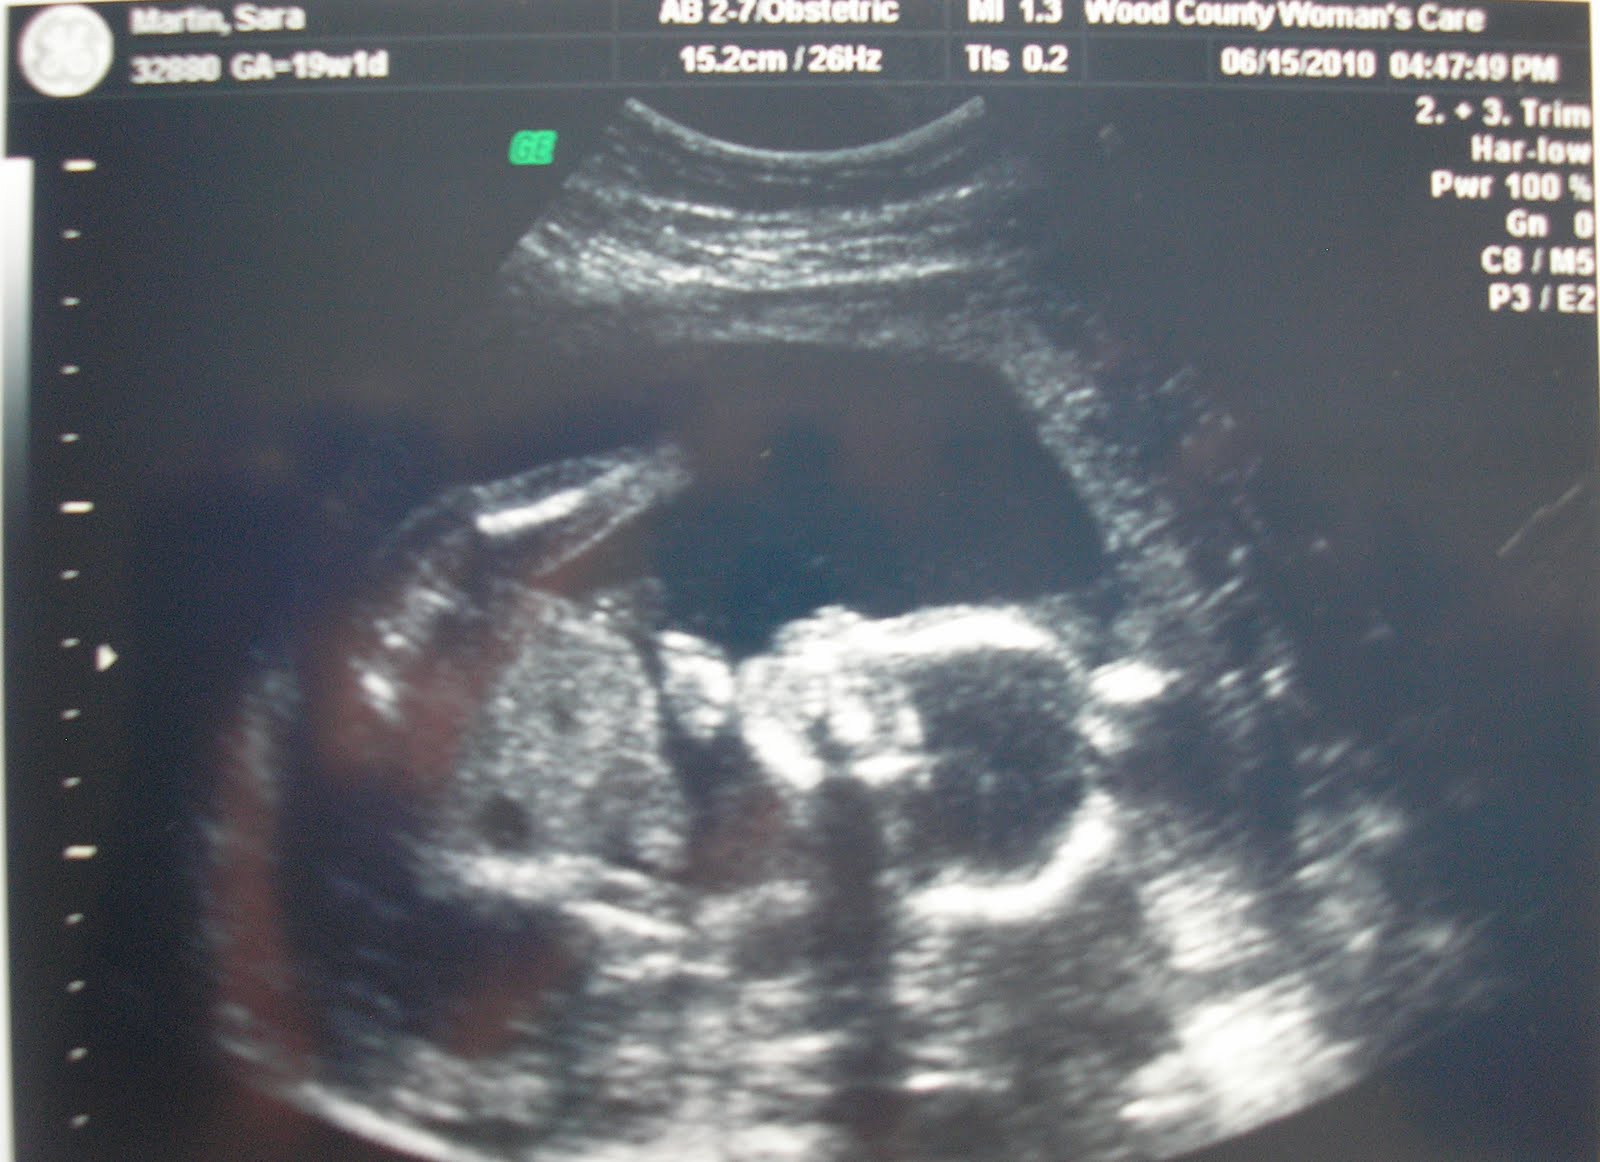

Well my dear blog-reading friends, seems like many of you (18 or 64% of you) were right on the money! We are having a GIRL! I am shocked and THRILLED. I was really thinking there was another little man in there. So thanks for your fun votes and speculations, accurate or not. We can't wait for our little girl. I'm gonna have a daughter.... :) :) :)

Here's a pic of me and my girl, halfway through our prenatal adventure. I've always heard fuss about super bad morning sickness and yada yada when you're pregnant with a girl, but I've gotta say, I've never felt better! What a blessing to be able to enjoy this pregnancy and still be in full effect for my 10 month old buddy. Thanks Lord for taking care of us. Yet again...